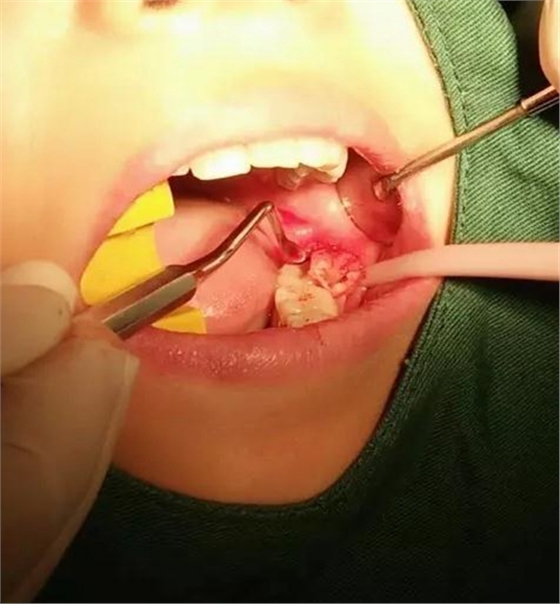

下面看一個(gè)病例,患者,女,30歲,因左下頜智齒嵌塞食物后疼痛,至當(dāng)?shù)匮揽平o予拔除,但術(shù)后1個(gè)半月,患者自覺(jué)拔牙區(qū)一直隱隱疼痛,時(shí)輕時(shí)重,遂來(lái)診。檢查發(fā)現(xiàn),拔牙創(chuàng)口一直未愈合,未見(jiàn)明顯腫脹,拍片發(fā)現(xiàn),拔牙窩內(nèi)顯示高密度斷根影

像,該斷根臨近下頜神經(jīng)管,同時(shí)發(fā)現(xiàn)第二磨牙遠(yuǎn)中有兩塊高密度影像,疑似殘留骨片或牙片,應(yīng)該是引起疼痛的原因,經(jīng)與患者溝通,采納建議,進(jìn)行二次拔牙。

挖匙取出

術(shù)中拍片發(fā)現(xiàn),還有剩余,繼續(xù)。。。。